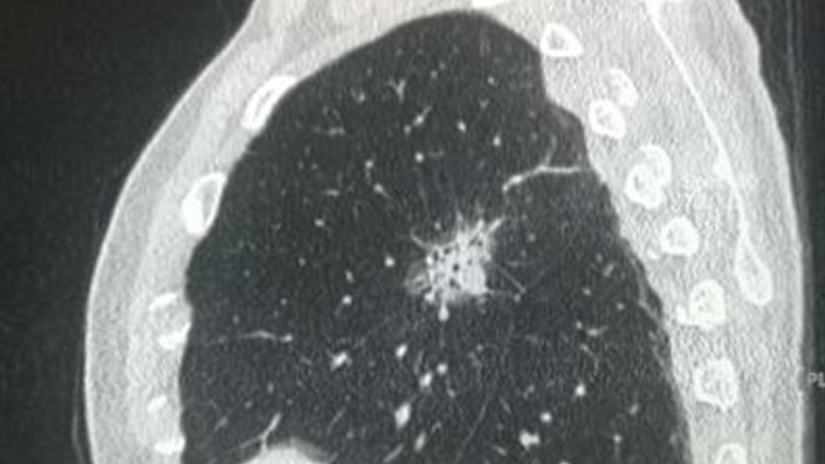

● 恶性结节

普遍长得比较嚣张且颜值低:有分叶、毛刺,分界不清,供血丰富。

这种结节看起来就像个刺头,一点都不老实,模糊分界是因为想往正常肺组织里扩张捣乱又不想太高调,丰富的供血可以悄咪咪地吸收周围组织营养让自己迅速生长。

▷ 结节边界不清,分叶、毛刺

▷ 结节大小≥8 mm

▷ 结节形态呈磨玻璃状(尤其是伴有实性成分的磨玻璃结节)

▷ 密度不均匀,实性成分高